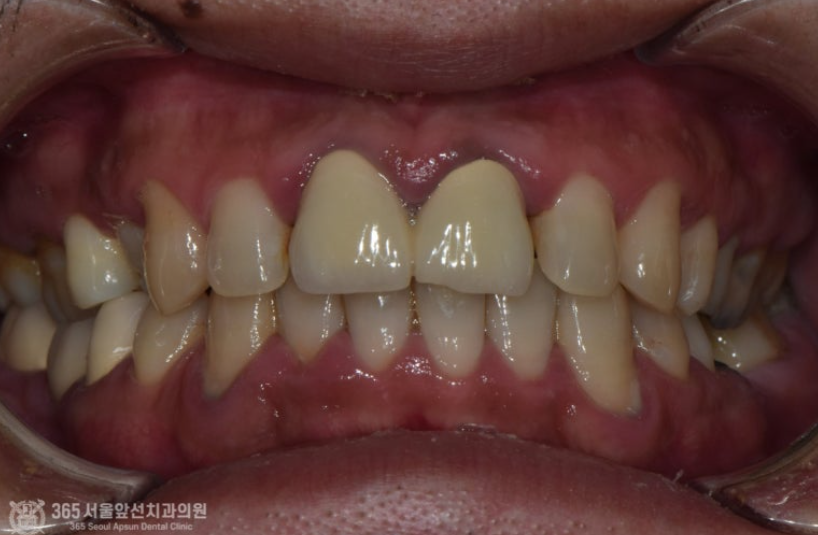

위쪽 앞니 보철물을 한지 오래됐는데, 바꾸고 싶어요. 안녕하세요. 주안역치과 365서울앞선치과 대표원장 강동우입니다. 오늘 소개해드릴 치료 증례는 앞니 보철물이 어색하다는 불편감으로 내원하신 환자분의 증례입니다~ 앞니는 치아의 기능도 중요하지만 무엇보다 심미성이 중요합니다. 쉽게 말해 앞니는 이쁜게 중요하다고 볼 수 있습니다 ㅎㅎ 촬영일시 : 2024.05.03. 처음 내원 당시 정면 모습입니다. 환자분께서 나이가 젊으셨음에도 불구하고 앞니의 보철물의 색상이 탁하고 어두워보이며 심지어 앞니 끝부분이 깨져있는것도 보입니다. 또한 PFM이라고 내부에 금속구조물을 포함한 보철물이다보니 금속 구조물이 빛의 투과를 막아 잇몸색이 탁한 색으로 보이는 우산효과(umbrella effect)도 관찰됩니다. 촬영일시 : 2024.05.03. 내원 당시 치료전 엑스레이입니다. PFM으로 제작된 앞니 보철물이 관찰되며, 치아 내부에 신경치료가 행해졌던 흔적도 보입니다. 환자분께서 증상은 따로 없으셨으나, 신경치료 상태가 불량하여 재신경치료도 진행하기로 했습니다. 촬영일시 : 2024.05.03. 재신경치료 중에 촬영한 엑스레이입니다. 정확하게 신경치료가 이루어지고있는것이 관찰됩니다. 촬영일시 : 2024.05.03. 재신경치료 후 엑스레이 사진입니다. 깔끔하게 충전된 양상이 관찰됩니다. 촬영일시 : 2024.05.03. / 2025.08.02. 이제 심미의 완성을 위한 잠정보철물(Provisional restoration)을 제작하여 환자분께서 원하는 형태를 찾아가며, 잇몸의 형태도 조절하는 과정(gingival molding)을 진행합니다. 환자분께서 심미를 중요시 여기는 분이셔서 두 번에 걸친 임시치아 제작 단계를 거쳐 최종적인 보철물을 만들었습니다. 촬영일시 : 2025.08.02. 완성된 최종보철물입니다. 깔끔하게 잘나왔습니다 어두웠던 잇몸색상도 개선되었습니다. 환자분께서도 만족하셨습니다 ㅎㅎ 촬영일시 : 2024.05.03. / 2025.08.02. 치료 전후 비교 모습입니다. 드라마틱한 변화가 관찰됩니다. 오늘은 오래된 앞니 보철물 교체에 관한 주제로 증례를 소개해드렸습니다. 앞으로도 좋은 치료로 보답하는 석바위시장치과, 365서울앞선치과가 되겠습니다 ! [ 치료기간: 2024년 5월3일 ~2025년 8월 2일 ] ※ 365서울앞선치과의원의 모든 포스팅은 각 진료과 의료진이 직접 작성합니다. 365서울앞선치과의원 블로그의 임상 케이스 게시물은 환자분께 의학적으로 정확하고 상세한 정보를 드리기 위해 각 진료과 의료진이 직접 작성하며, 모든 증례 사진은 본원 의료진이 직접 시술한 증례를 촬영한 것으로, 의료법 제23조, 제56조에 의거하며 환자분의 동의를 얻어 포스팅에 사용하였습니다. 또한 해당 케이스는 본 환자분의 치료 결과이며, 환자 상태에 따라 치료의 결과는 달라질 수 있습니다. |